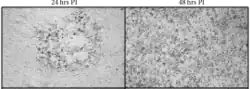

| B virus spread in murine cells with time at 24 and 48-hours post infection (PI) | |